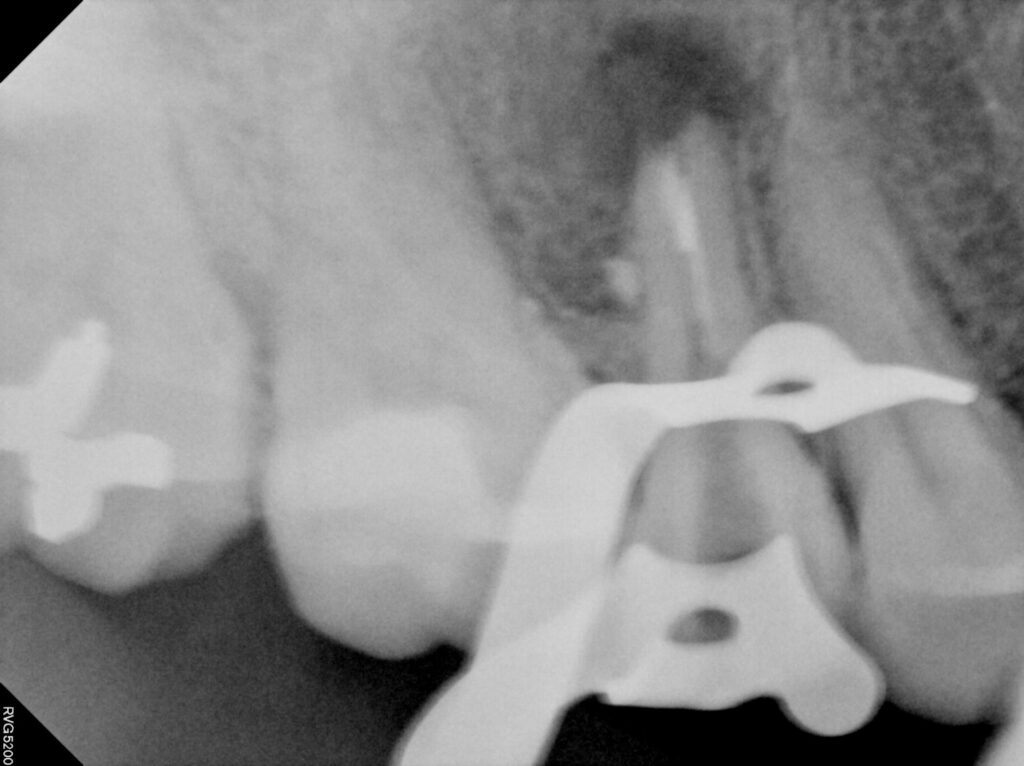

이후 치근단 절제술을 시행하였는데요.

사이즈가 너무 크다 보니 보통은 잘 하지 않지만

뼈이식을 함께 진행하였습니다.

치근단절제술은 치아 뿌리 끝에 생긴

염증이나 낭종을 외과적으로 제거하는 수술로

보통 신경치료를 받은 후에도 뿌리 끝 주변 조직에

세균이 침투하거나 치근관의 해부학적 구조가 복잡해

약물이 끝까지 도달하지 못할 때 시행됩니다.

재신경치료로 해결되지 않는 경우에 한해

치아의 뿌리 끝을 절제해 염증 부위를

직접 정리함으로써 통증과 감염을 차단하는 것이 목적입니다.